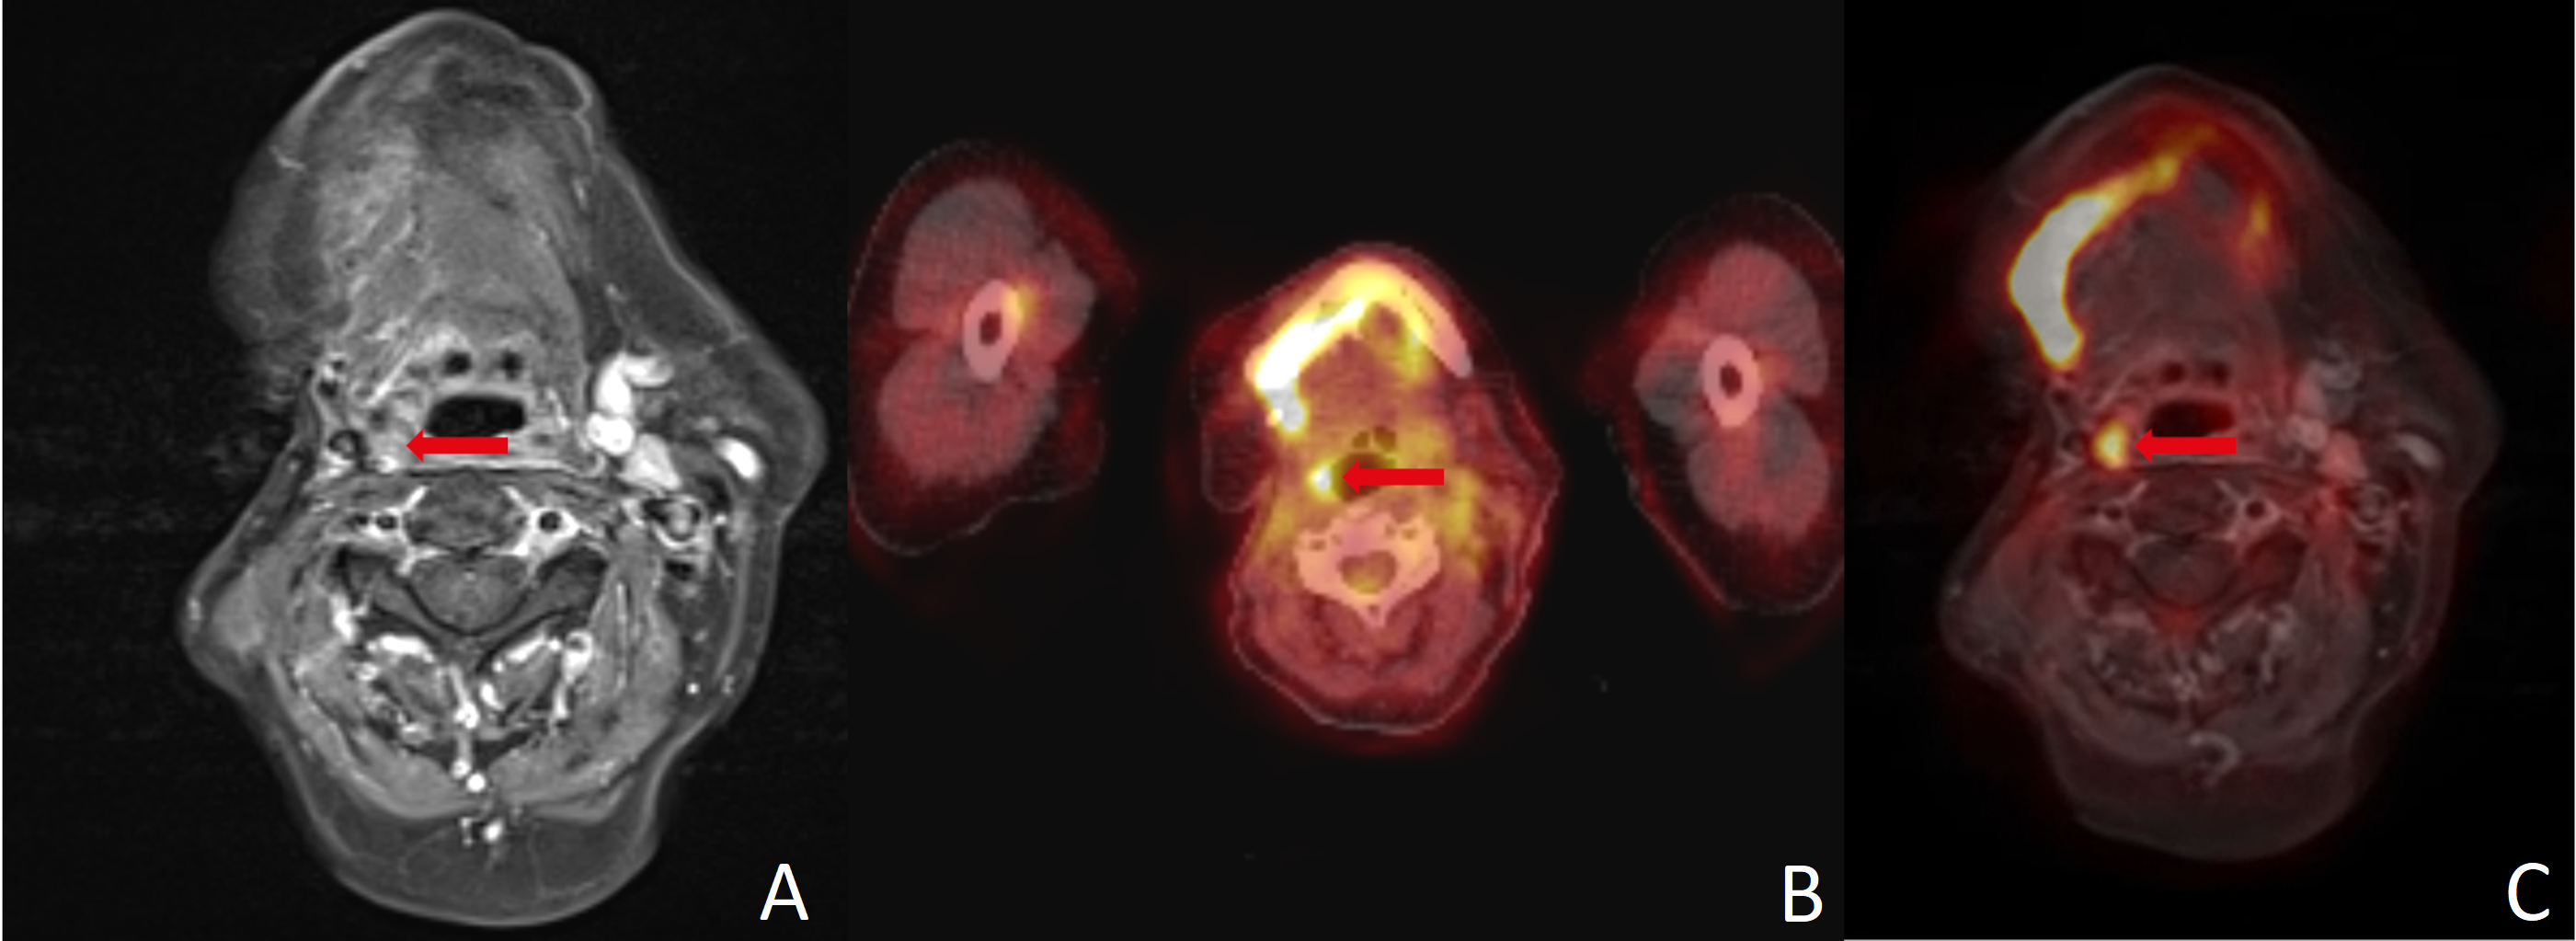

Figure 2.

(A) MRI yielded a false negative finding, whereas (B) PET/CT, (C) PET/MRI and histopathology all confirmed malignancy. The FDG uptake combined with high soft-tissue contrast in (C) PET/MRI can simplify image interpretation and help guide surgery. Red arrows point to the region of interest in all three imaging modalities.

3.3. Intersection of False Results

Patients with malignancy confirmed by histology were assessed as false negative in five (13.5%) cases by MRI, in five (13.5%) cases by PET/CT and in five (13.5%) cases by PET/MRI (see Figure 2). In one (2.7%) case, both MRI and PET/CT were false negative and PET/MRI identified a suspicious lymph node. Conversely, one (2.7%) patient was diagnosed false negative in PET/MRI, while MRI and PET/CT detected a suspicious finding (see Figure 2).

A major limitation of nearly all imaging methods is the detection of small LNMs. Yamazaki et al. found true positive LNMs in PET/CT to have a mean diameter of 13.4 mm, whereas false negatives had a mean diameter of only 3.1 mm [32]. Accordingly, they described the diagnostic accuracy to be poor in nodes smaller than 10 mm [32]. The challenge in this respect is that a large proportion of LNMs are smaller than this margin [33]. Since MRI attempts to overcome this limitation using DWI and DCE, it appears promising to combine PET with DCE-MRI. However, our data did not provide evidence for improved assessment of small nodes, although in one case FDG-PET could reveal LNM in a positive neck that was not registered in MRI (see Figure 2). Interestingly, elevated risk of LNM in histology (T classification ≥ 3, lymphatic invasion, grading ≥ 3 and/or p16 positivity) seems to be associated with a higher risk of divergent results in different imaging modalities, since only one of seven patients with divergent imaging results did not have elevated risk in histology.